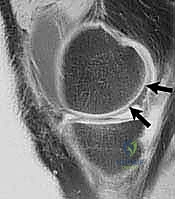

- التصوير بالرنين المغناطيسي (MRI): هو المعيار الذهبي لتشخيص إصابات الغضروف. يوفر صوراً عالية الدقة للأنسجة الرخوة، ويسمح للدكتور هطيف بتحديد حجم، عمق، وموقع العيب الغضروفي بدقة مليمترية، بالإضافة إلى تقييم حالة العظم تحت الغضروفي والأربطة.

يُصنف هذا الإجراء تحت فئة "تحفيز نخاع العظم". عندما يكون هناك عيب غضروفي كامل السمك (أي أن العظم مكشوف تماماً)، يقوم الجراح باستخدام أداة دقيقة تشبه المخرز (Awl) لعمل ثقوب صغيرة في هذا العظم المكشوف.

هذه الثقوب تخترق الطبقة العظمية الصلبة (Subchondral bone plate) وتصل إلى نخاع العظم الغني بالأوعية الدموية. نتيجة لذلك، تخرج من هذه الثقوب قطرات من الدم والدهون تحتوي على مكونات سحرية: الخلايا الجذعية الميزنكيومية (Mesenchymal Stem Cells - MSCs) وعوامل النمو القوية.

تتجمع هذه المكونات في منطقة العيب الغضروفي (التي تم تنظيفها مسبقاً لتصبح مثل وعاء صغير) لتشكل ما يُعرف بـ "الجلطة الدموية الفائقة". هذه الجلطة هي الأساس البيولوجي للشفاء. بمرور الأسابيع والأشهر، وتحت تأثير الحركة الميكانيكية المدروسة (التأهيل)، تتمايز هذه الخلايا الجذعية وتتحول الجلطة إلى نسيج جديد يسمى النسيج الليفي الغضروفي (Fibrocartilage).